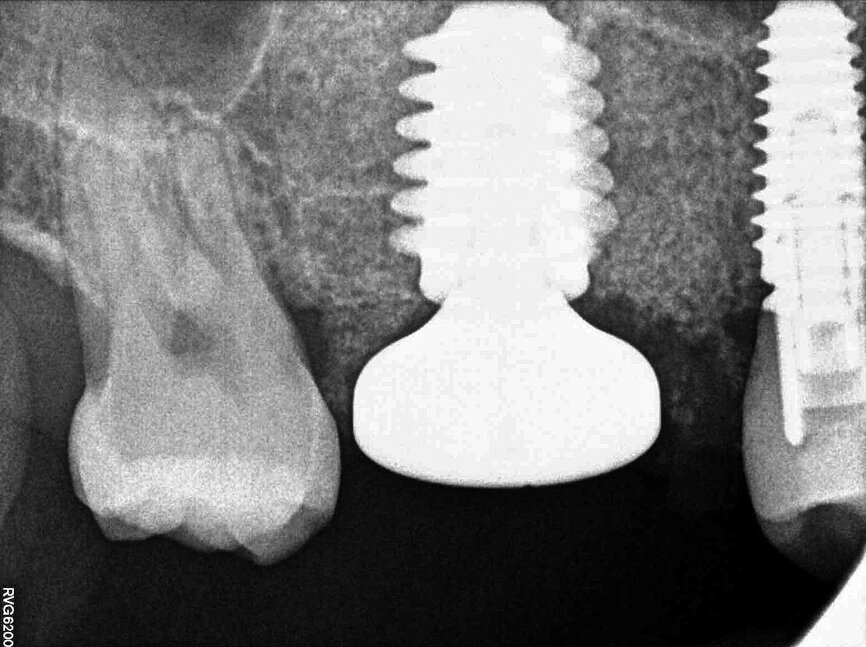

In November 2017, a 39-year-old female patient came to an initial appointment at White Clinic owing to tooth pain (tooth #16). A clinical and radiographic examination were performed, including a periapical radiograph, CBCT scan (Carestream 9500, Carestream Dental), and intra- and extraoral photographs (Figs. 1–3).

In the clinical and radiographic evaluation, it was observed that tooth #16 presented an invasive cervical resorption at the mesiobuccal root. The treatment plan established was dental extraction with immediate implant placement. The tooth had been previously re-treated endodontically and restored with a definitive ceramic crown. Due to the current situation of the tooth, although the protocol in White Clinic is to preserve teeth, it had indication for immediate extraction. Also due to the lack of time, our digital team was not able to produce a surgical guide for the implant placement. Therefore, the treatment plan included a surgical phase and a digital prosthetic phase.

Once the implant bed had been prepared, a 7 × 10 mm implant (AnyRidge) was placed. After placement, the ISQ (Implant Stability Quotient) was measured with a stability meter (Mega ISQ, MegaGen), and the value was 72. According to the ISQ scale, this represents high stability (Fig. 6b). A 10 × 7 mm healing screw (AnyRidge) was placed, along with a plug of A-PRF (advanced platelet-rich fibrin; PRF process by Choukroun) in order to accelerate the healing process, and sutured with 4/0 polypropylene (Hu-Friedy; Figs. 7–10). After the surgical procedure, the White Clinic postoperative protocol was applied: application for eight minutes of the ATP38 laser (Swiss Bio Inov), based on the principle of Low Level Laser Therapy that acts on the cellular metabolism and provides a better and faster postoperative healing. The patient was instructed to use a 0.2% hyaluronic acid gel (Gengigel, Ricerfarma) and 0.1% hyaluronic acid mouthwash (Gengigel First-aid, Ricerfarma) for one week after surgery, with the goal of accelerating the healing process. One week after surgery, the sutures were removed, ozone was used to disinfect the area around the implant, and the ATP38 was applied for eight minutes to promote healing.